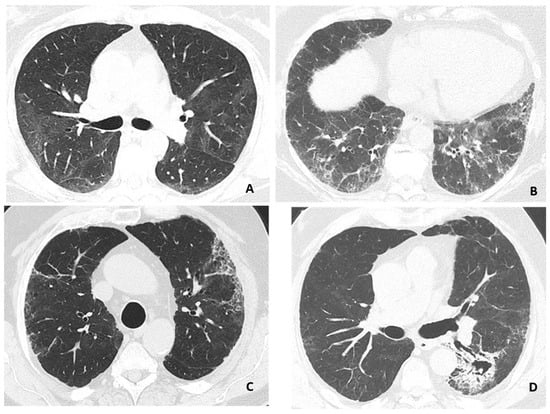

3.2. HRCT